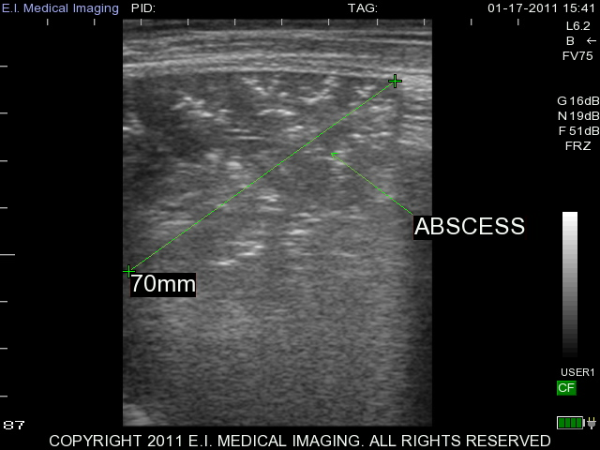

My name is Elizabeth Adams and I am a dairy practitioner in the central valley of California. Recently, I was able to use the IBEX PRO portable ultrasound to look at calf lungs for evidence of damage from calfhood pneumonia. In veterinary school, I scanned all of my patients with respiratory symptoms because it is a fast, non-invasive exam that provides a lot of information quickly. With ultrasound I can see healthy lungs, pleural effusion, atelectasis, consolidation and abscessation.

Ultrasound allows me to look at the surface of the lung; in a healthy lung, this is all we can see as the lung is full of air and doing its job. In a diseased lung, the surface of the lung is abnormal and allows penetration of the ultrasound waves deep into the lung parenchyma. Young calves require only the penetration of a 5-7.5MHz rectal ultrasound probe to see the evidence of damage from previous pneumonia.

It is very important to take measures to prevent calfhood pneumonia and to recognize and treat the disease early. With all of our preventative measures, there will always be some animals that develop a chronic pneumonia. If calves are sent to a custom calf raiser, the client may not know which of his animals have been treated multiple times for pneumonia. As feed costs continue to rise, I believe it is important to make wise investments when selecting animals.